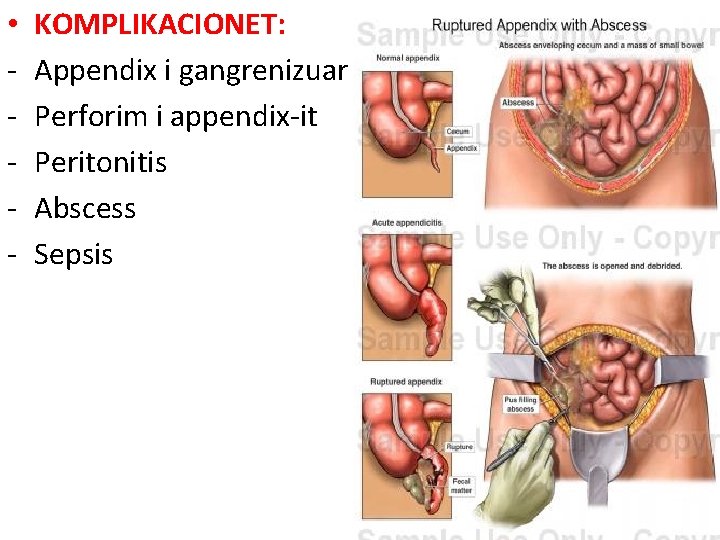

• - KOMPLIKACIONET: Appendix i gangrenizuar Perforim i appendix-it Peritonitis Abscess Sepsis